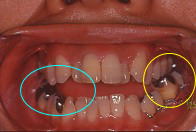

(3)噛み合わせ(咬合)の確認

歯の脱臼、変位・転位、顎の骨の骨折が有ると、噛み合わせに変化が生じます。

1)口の開き方----開口量、開口時の痛みなどを確認して下さい。

2)咬み合わせ---かみ合わない場合は、骨折が疑われます。

右側 左側

左は咬んでいるのに、右は咬んでいません。

噛み合わせを見るだけで、左側が折れているのが分かります。